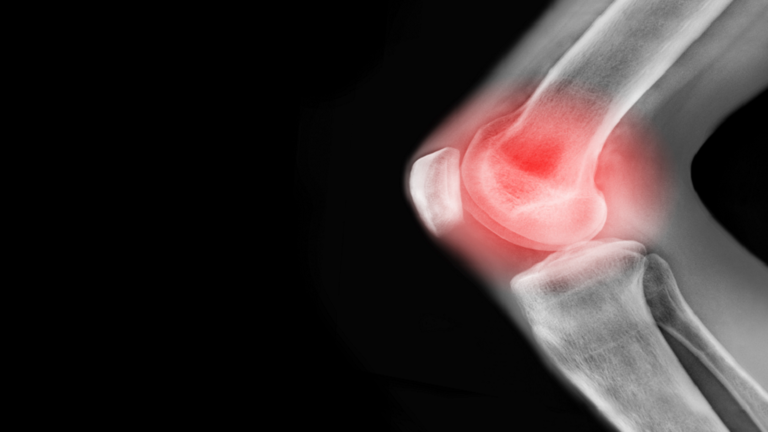

ما أسباب آلام الركبة وكيف يمكن علاجها؟!

يمكن أن يؤثر ألم الركبة المزمن على نشاطك، ويقول الخبراء إن التمارين الأساسية يمكن أن تساعد بشكل كبير في معظم مشاكل الركبة.

وفي معظم الحالات، يتمثل سبب آلام الركبة في الصدمة الناجمة عن إصابة رياضية أو إصابة في العمل.

ويعد تلف الغضروف داخل الركبة وتمزق الأربطة، من الإصابات الشائعة التي تحدث بسبب الصدمة.